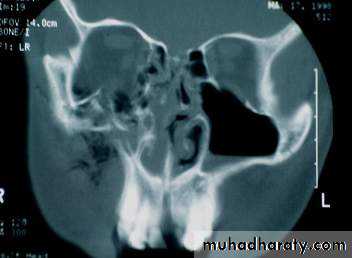

• CT Scan

• 1.5 mm cuts

• axial and coronal views

Water’s ViewCT Scan

• Radiographic findings:

• Fracture line which involves• Nasal aperture

• Inferior maxilla

• Lateral wall of maxilla

• CT of the face and head

• coronal cuts

• 3-D reconstruction

Radiographic imaging:Fracture involves:

Nasal bones

Medial orbit

Maxillary sinus

Frontal process of the maxilla

CT of the face and head